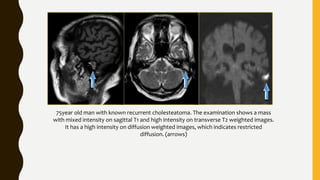

75year old man with known recurrent cholesteatoma. The examination shows a mass

with mixed intensity on sagittal T1 and high intensity on transverse T2 weighted images.

It has a high intensity on diffusion weighted images, which indicates restricted

diffusion. (arrows)